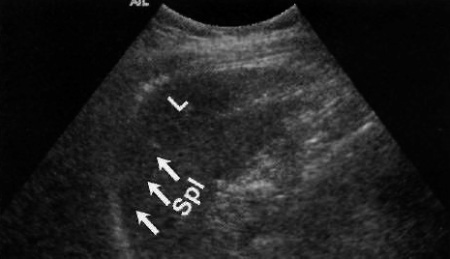

Фото 7. Ложноположительный результат УЗИ: нормальная левая доля печени (L) пересекает срединную линию и проецируется над селезенкой (Spl), тем самым имитируя околоселезеночную гематому. Стрелками обозначена граница печени и селезенки